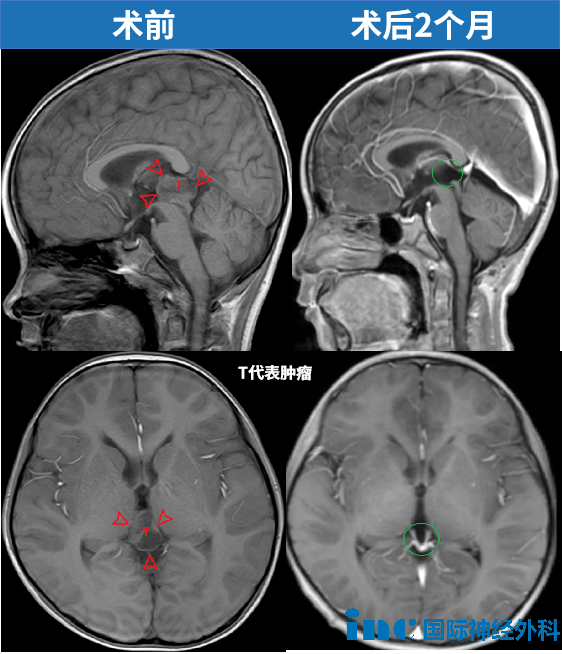

以INC巴特朗菲教授在北京天坛医院完成的一台手术为例:一名6岁男童意外跌倒后送医检查,结果发现松果体区存在一处大小约22×14×17毫米的肿瘤。巴特朗菲教授主刀为这名患儿实施了精准切除,术后孩子功能完全无碍,已顺利回归校园生活。与其他案例一样,这样的结果并非偶然,而是建立在精准评估、精细操作与充分医患沟通基础上的必然。